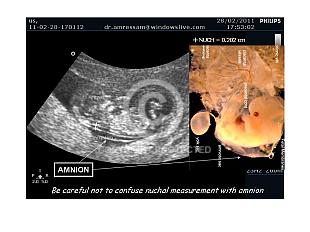

Nuchal Translucency